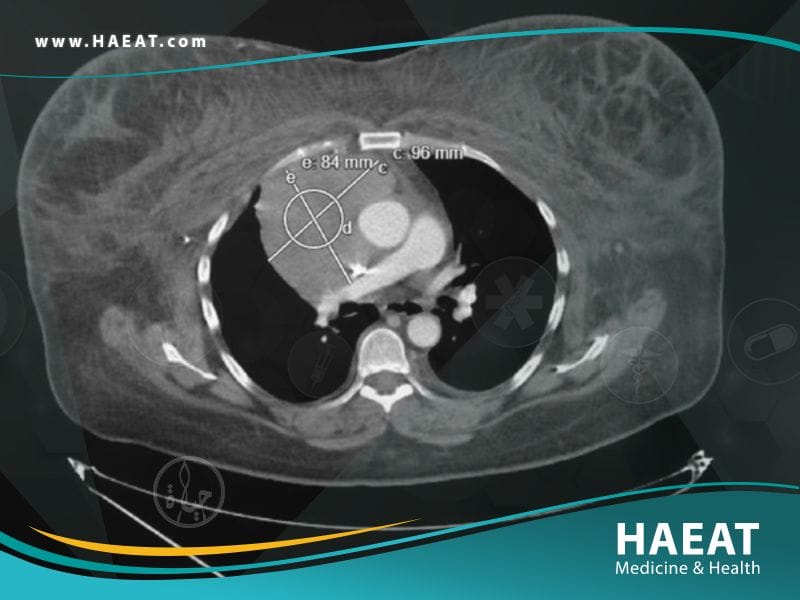

- عمل أشعة مقطعية شاملة لمنطقة الصدر.